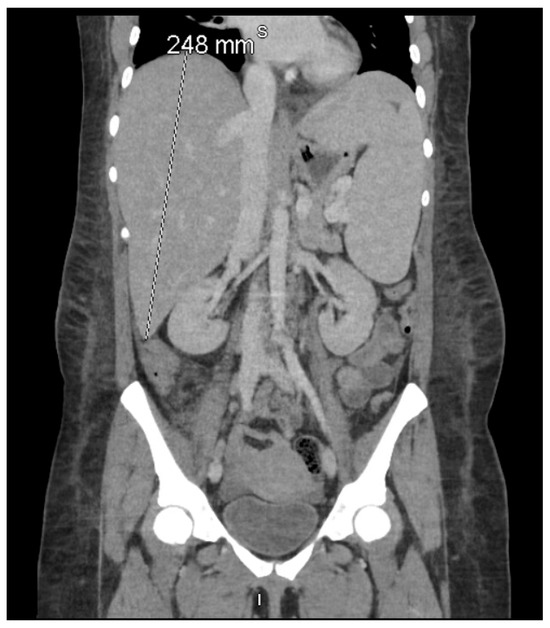

Upon transfer to our tertiary center on 11 December 2024, she appeared markedly more fragile and lethargic, with ECOG performance status declining to 3, accompanied by dyspnea on minimal exertion, profound asthenia, and symptomatic anemia. Laboratory evaluation showed severe pancytopenia (hemoglobin 5.3 g/dL, platelets 86 K/μL, absolute neutrophil count 1.01 K/μL), worsening hyperbilirubinemia (total bilirubin 15.1 mg/dL), elevated lactate dehydrogenase (362 U/L), and extreme hypertriglyceridemia (1114 mg/dL). Reevaluation uncovered hepatosplenomegaly (Figure 1) and hyperferritinemia that had escalated to 16,375 μg/L by December 12. sIL-2R levels measured on December 13 surged to 10,765 pg/mL (normal: 175–858 pg/mL), fulfilling six HLH-2004 criteria: fever (≥38.5 °C), splenomegaly, cytopenias (hemoglobin <9 g/dL, platelets <100 K/μL), hyperferritinemia [>500 (ng/mL]), hypertriglyceridemia (>250 mg/dL), and elevated sIL-2R. Bone marrow biopsy excluded lymphoma, and bone marrow cultures for bacteria, virus, fungus, and acid-fast bacillus (AFB) stain were negative.

Figure 1. Coronal contrast-enhanced computed tomography (CT) of the abdomen and pelvis demonstrating pronounced hepatosplenomegaly, with the liver measuring 248 mm craniocaudally and the spleen measuring 186 mm in its long axis. According to the HLH-2004 criteria established by the Histiocyte Society, splenomegaly—clinically defined as palpable ≥2 cm below the left costal margin and radiologically as a CT spleen length >12 cm—is one of eight diagnostic features, of which at least five must be fulfilled for HLH diagnosis [6]. This imaging finding, together with extreme hyperferritinemia (16,375 μg/L) and hypertriglyceridemia (1114 mg/dL) on 11–12 December 2024, fulfilled the hepatosplenomegaly criterion in both the HLH-2004 diagnostic criteria [6] and the revised HLH-2024 guidelines [16].